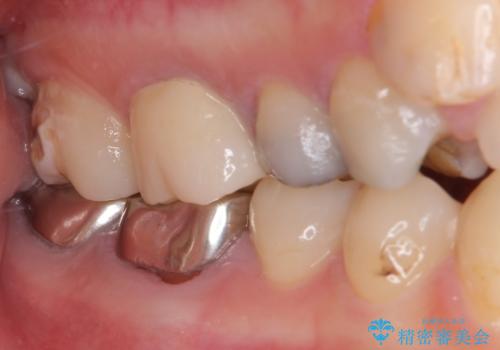

- 笑ったときに見てしまう上顎奥歯の銀歯を気にして来院された患者様です。

折角セラミッククラウンを装着するので、根管治療を行った後に補綴治療を行うこととしました。

他にも目立つ銀歯がありましたが、最も気にしている2本を優先して行うこととしました。

結婚式前にはクリーニングやホワイトニングを行い、その後他の歯を治療していく予定です。